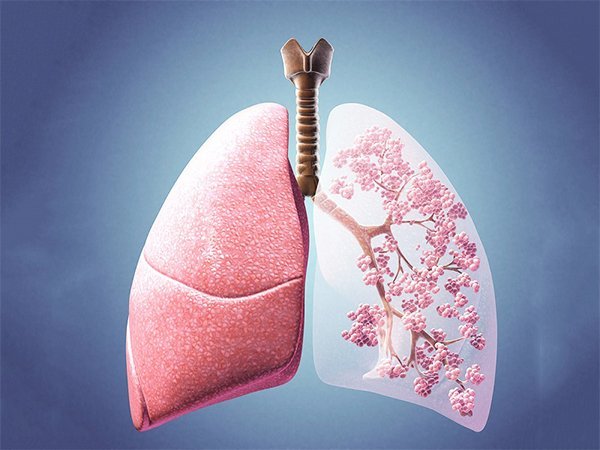

مهندسین زیست پزشکی دانشگاه کیس وسترن رزرو آمریکا با تحریک سلول ها برای تشکیل سه نوع بافت مجزا و سپس سازماندهی آن ها درون ساختارهای لوله ای شکل توانستند نای مصنوعی تولید کنند.به گزارش بهداشت نیوز، نای که معمولا آن را مجرای هوایی می نامند بین حنجره و ریه ها قرار گرفته است و بیماران معمولا به دلایلی مانند برداشتن تومور و یا استونوزیس نایی دچار آسیب می شوند که این امر نای را تنگ یا منقبض می کند و نفس کشیدن فرد را دچار مشکل می کند.آسیب به این عضو حیاتی می تواند کشنده باشد و یا این که کیفیت زندگی فرد را به طور قابل ملاحظه ای کاهش دهد و معمولا راه حل های محدودی برای نای آسیب دیده وجود دارد و اگر بخشی از آن آسیب ببیند، تنها با جراحی قابل برداشت است و باید به دنبال راهی برای جایگزین کردن بخش آسیب دیده بود.استفاده از رویکردهایی مانند ایمپلنت کردن یک استنت یا برداشتن بافتی که موجب انسداد مجرای هوایی می شود، مسکنی کوتاه مدت برای این مشکل خواهد بود و استفاده از رویکردهای مهندسی بافت و مواد طبیعی یا سنتتیک به عنوان داربست برای سلول ها نیز با چالش هایی مانند عدم کشت یکدست سلول ها روی داربست و غیره با مشکلاتی مواجه است.به عقیده محققین Case Western Reserve، جایگزین نای جدید باید سفتی لازم برای جلوگیری از کولاپس کردن (بسته شدن) در زمان تنفس را داشته باشد و اپی تلیوم تنفسی حفاظت کننده ایمنی رطوبت لازم را در مجرای هوایی فراهم کند و همچنین عملکرد مجرای هوایی را حفظ کند و به عنوان سدی برای ورود پاتوژن ها و ذرات خارجی عمل کند.مهندسین زیست پزشکی حلقه های خودسازمان یافته ای را تولید کرده اند که هر سه فاکتور بالا را دارا هستند و می توانند با یکدیگر ادغام شوند و لوله هایی حاوی غضروف ها و بافت های پیرامون عروقی را شکل دهند و حلقه غضروفی حاصل تجمع سلول های بنیادی که مشتق از مغز استخوان در ظروف حلقه ای شکل است، میکروسفرهای پلی مری حاوی پروتئین و سلول های بنیادی را برای تبدیل شدن به کندروسیت ها القا می کنند.اما حلقه پیرامون عروقی حاوی سلول های بنیادی مشتق از مغز استخوان و سلول های اندوتلیالی است که لوله نای مهندسی شده حاوی این حلقه های غضروفی و پیرامون عروقی است و با سلول های اپی تلیالی پوشیده شده که با استفاده از این رویکرد، توانسته اند نای هایی با قدرت الاستیسیتی بالا را در اندازه های مختلف بسازند.ایمپلنت نای مهندسی شده زیر پوست موش، حاکی از برقراری ارتباط بین ساختار پیرامون عروقی نای با منبع خونی میزبان بوده است و محققین امیدوارند بتوانند از این ایمپلنت مهندسی شده در آینده ای نزدیک برای جایگزین نای آسیب دیده بیماران استفاده کنند.